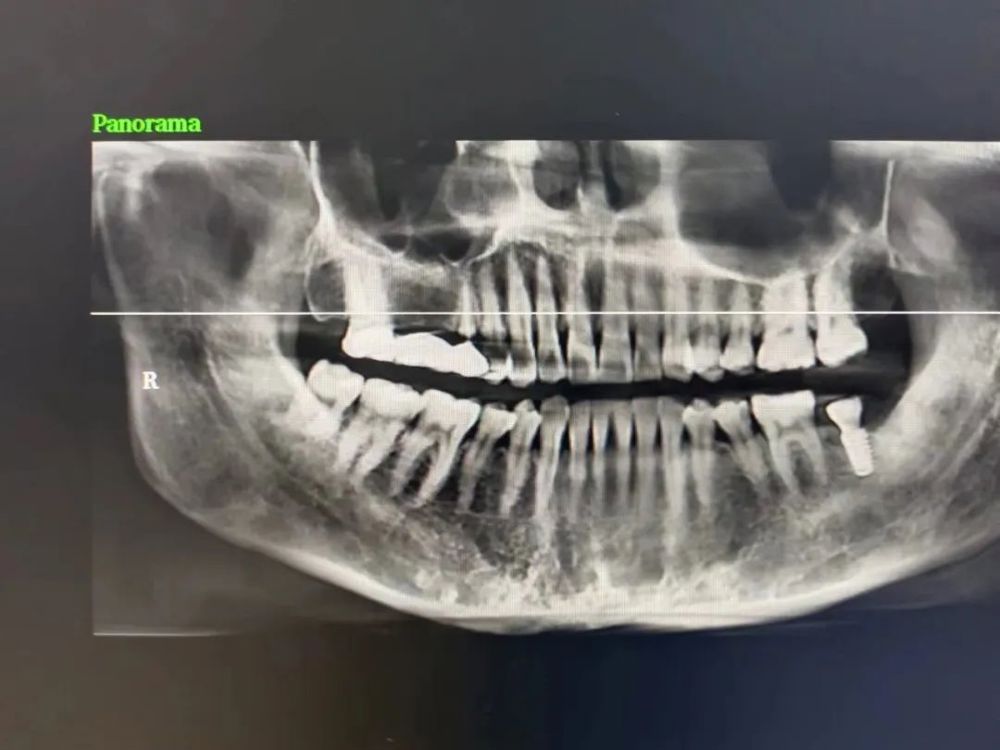

案例(lì)二

種植前 種植後